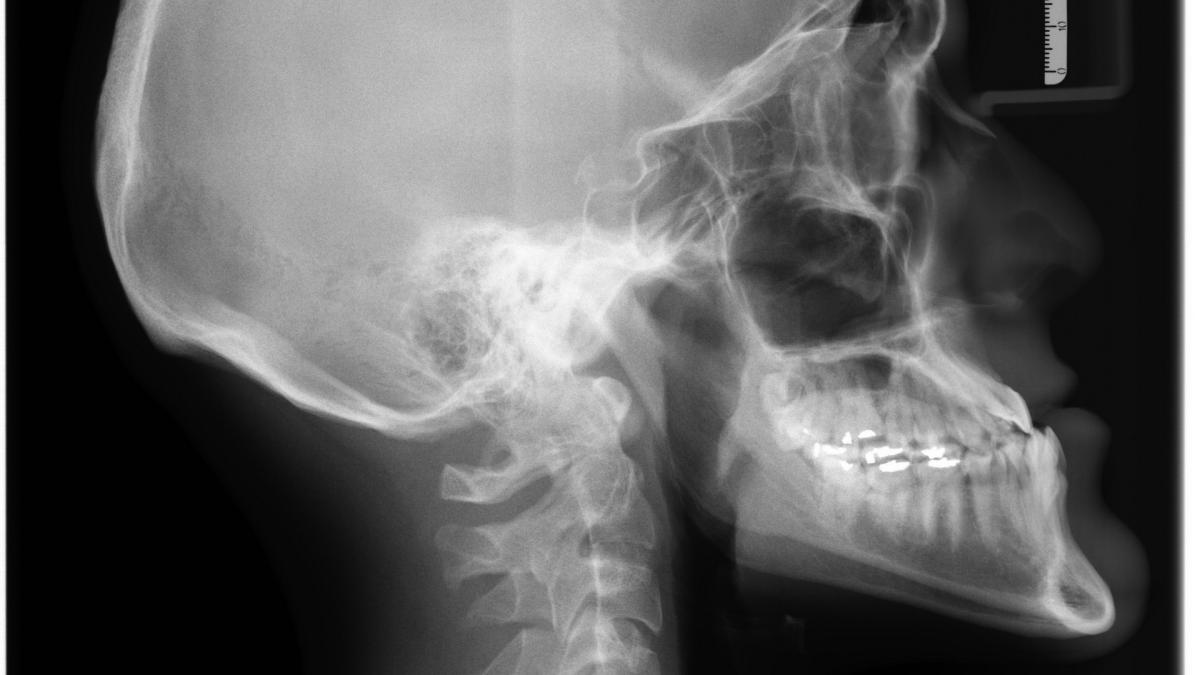

convulsii-parazit-in-creier_32763100 Foto cu caracter ilustrativ: Pixabay

Un bărbat care s-a internat în spital cu convulsii a descoperit că un parazit îi invadase creierul.

Medicii care au tratat un bărbat internat în spital cu convulsii, dezorientare și comportament ciudat au descoperit, după mai multe analize, că acesta a trăit în ultimii ani cu larve de tenii în creier, potrivit unui studiu de caz publicat pe 11 noiembrie în New England Journal of Medicine.

Bărbatul de 38 de ani părea să fie într-o stare perfectă de sănătate, până într-o noapte când soția sa l-a găsit pe podea, tremurând și vorbind bizar, potrivit raportului cazului. A fost internat în spital, iar medicii l-au tratat pentru convulsii, observând că nu răspundea la întrebări și părea să privească involuntar spre tavan. Acesta nu avea antecedente de boală, nici medicamente sau consum de droguri și nici simptome recente până la apariția convulsiilor, a spus familia sa medicilor scrie Business Insider, citează observatornews.ro.

Echipa medicală de la Spitalul General din Massachusetts a diagnosticat în cele din urmă pacientul cu cisticercoză, altfel cunoscută sub numele de infecție cu tenie, care a fost confirmată prin scanări ale creierului și analize de sânge.

Cu două decenii mai devreme, pacientul emigrase dintr-o zonă rurală din Guatemala, unde bolile legate de paraziți sunt endemice, potrivit studiului de caz.